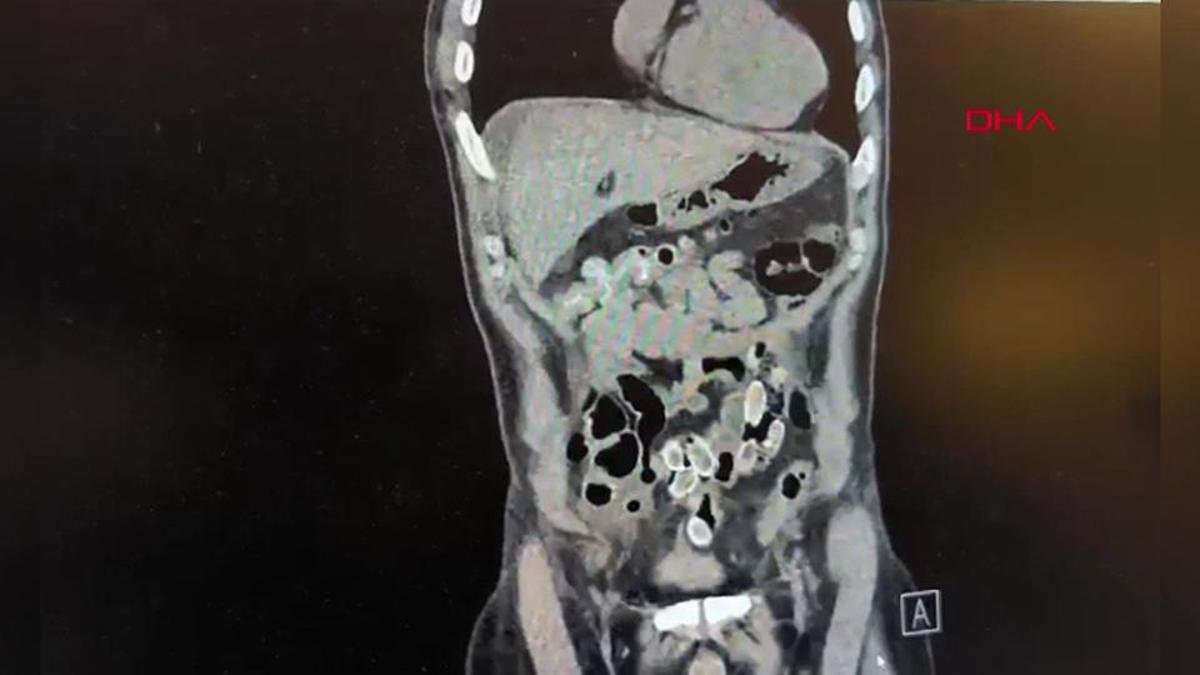

Hastane yetkilileri durumu polise ekiplerine bildirdi. Hızla ameliyata alınan şüphelinin midesinden 49 adet paketlenmiş, toplam 259 gram ağırlığında uyuşturucu madde çıkarıldı.